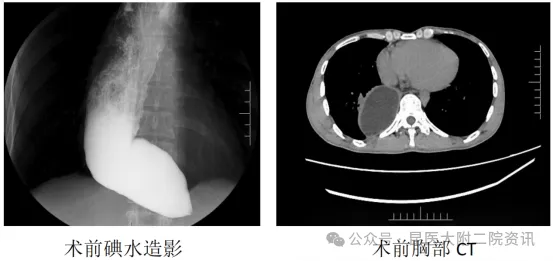

患者李某,男,37岁,因反复吞咽困难10余年入院。胃镜提示贲门失弛缓症、食管潴留;上消化道造影见食管蠕动差,食管下段及贲门部鸟嘴样狭窄,其上端食管明显扩张、潴留;胸部CT见食管全程明显扩张积液、移位至右肺后伴右肺下叶外压性不张。消化内科一病区李俊主任团队对患者病情进行充分讨论和认真分析,认为患者病史长、食管扩张、肺部受压明显,实施手术难度高、风险大,但对患者来说,经口内镜下肌切开术(POEM)手术,可以在保留正常解剖结构的同时,创伤小,并可取得与外科手术相似的疗效。在与患者及家属充分讲解病情、介绍POEM手术的优缺点及相应麻醉、手术风险后,患者及家属认可李俊主任团队协同麻醉手术科制定的麻醉和手术计划,愿意进行POEM手术。

术后碘水造影

6月24日,李俊主任为患者顺利实施全麻气管插管下经口内镜下肌切开术(POEM),耗时近2小时,术后禁食48小时,予以抑酸护胃、预防性抗感染、营养支持等治疗,复查上消化道碘水造影见食管下段及贲门已扩张,造影剂通过顺畅、食管扩张较术前减轻,未见造影剂漏入隧道或其他部位,患者开放流质饮食后进食顺畅。目前患者已恢复出院。